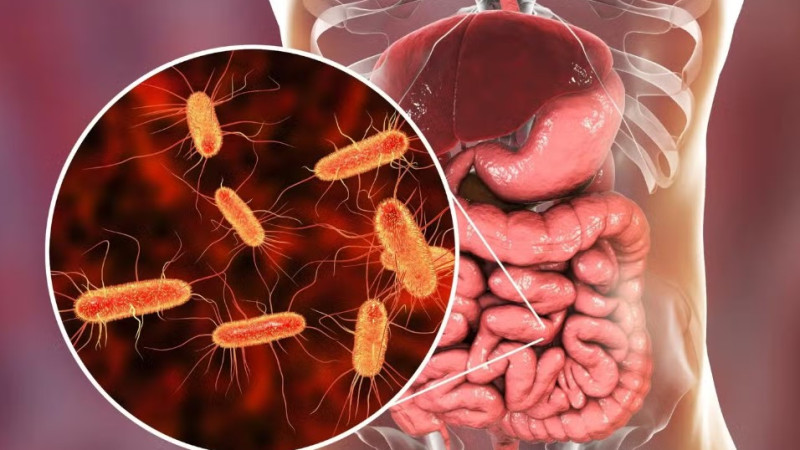

Снимок УЗИ

Реальное фото с ультразвукового исследования, сделанного в 1991 году.